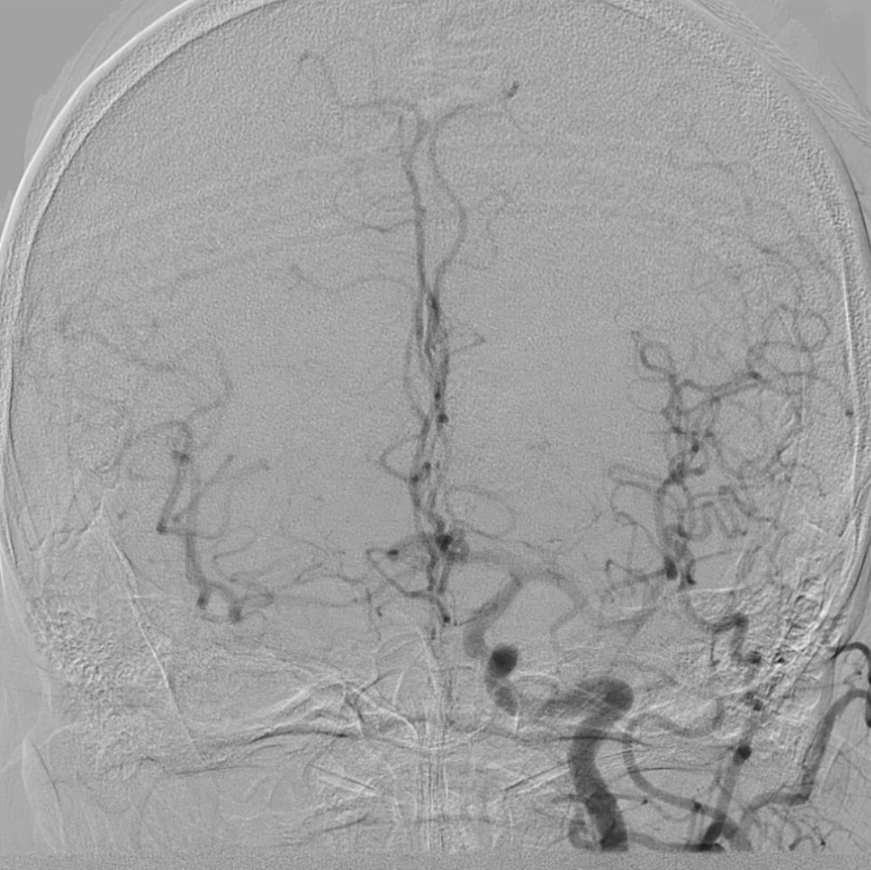

造影显示:支架膨胀良好,无需后扩张;

颅内血供:左侧颈内动脉血流通畅,因右侧闭塞,左侧成为全脑主要供血通路,血供恢复满意